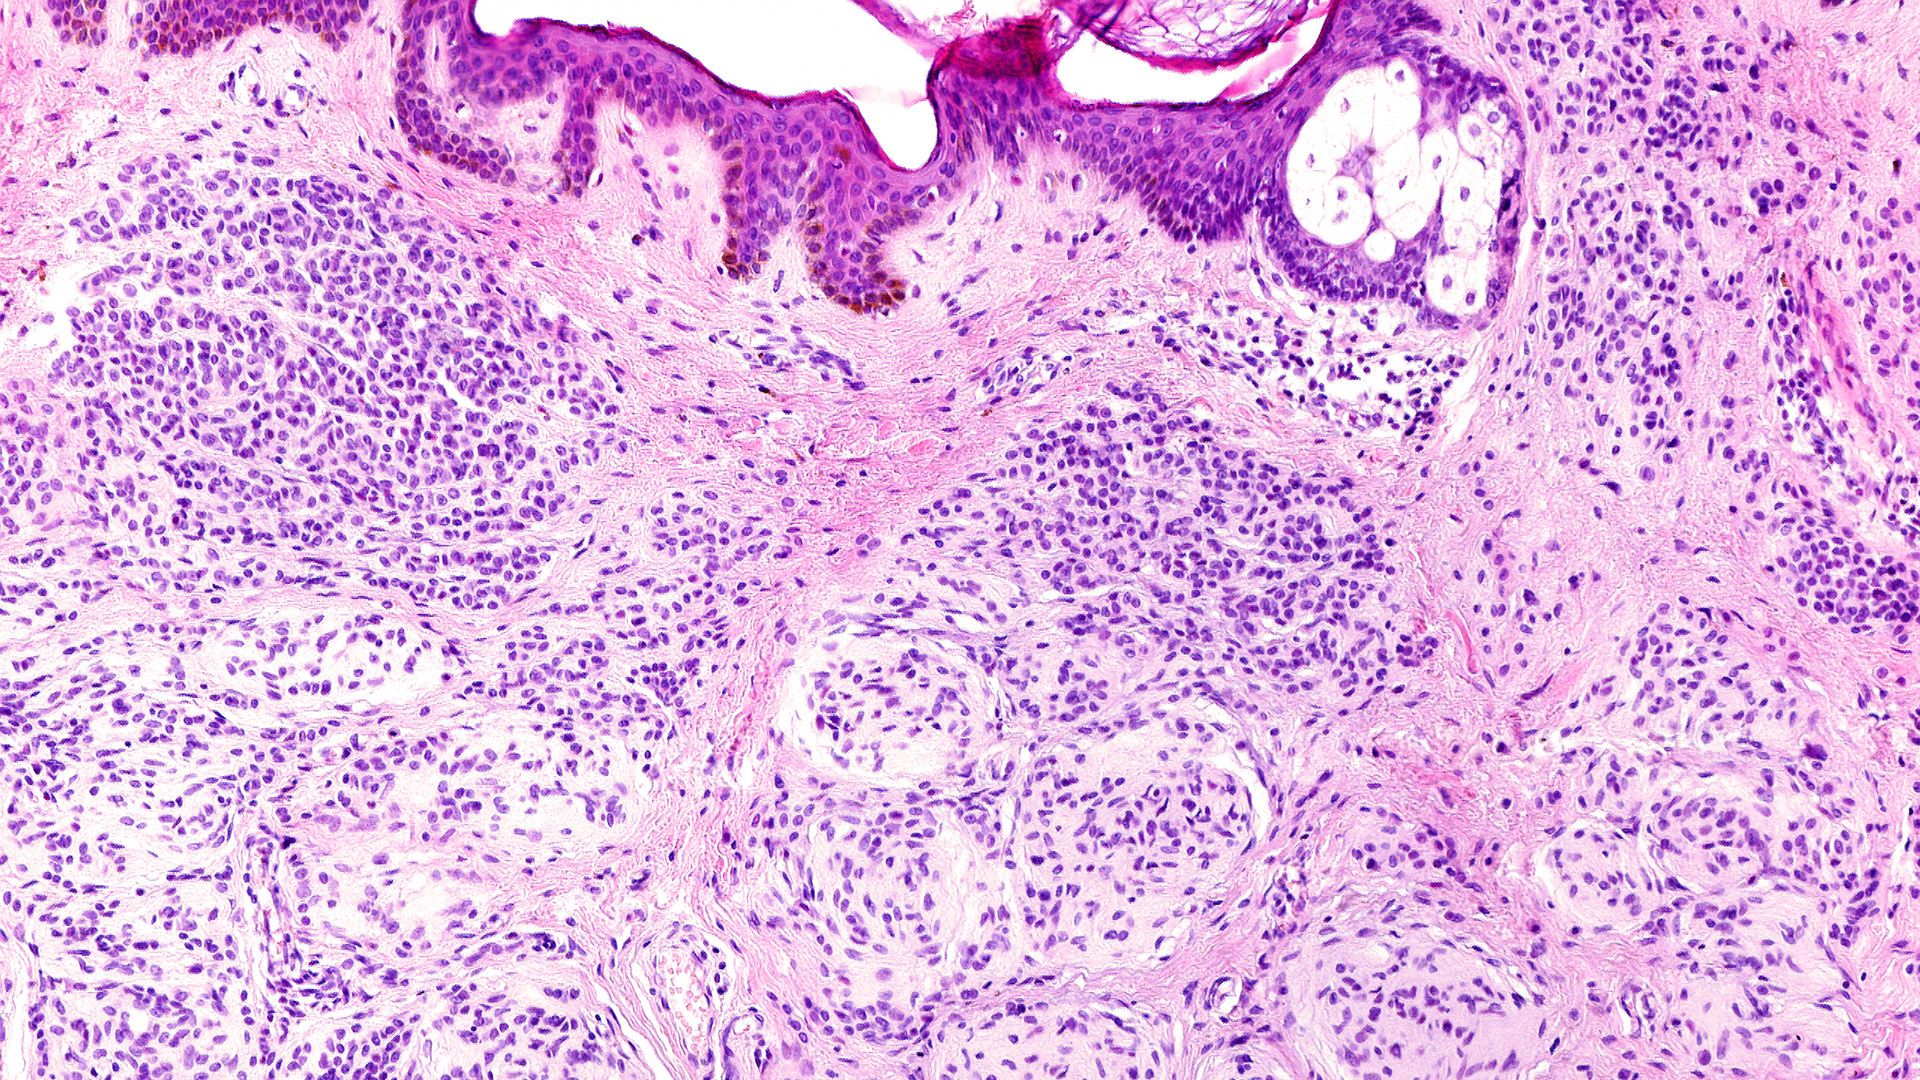

Vorkommen von unverhorntem Plattenepithel

Überall dort, wo Sperma hinkommt

= Vagina, Mundhöhle, Oesophagus, Anus, Stimmfalten